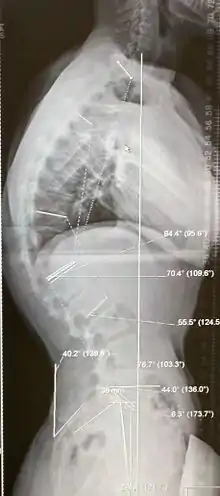

Diagnosis is typically by medical imaging. The degree of kyphosis can be measured by Cobb's angle and sagittal balance.